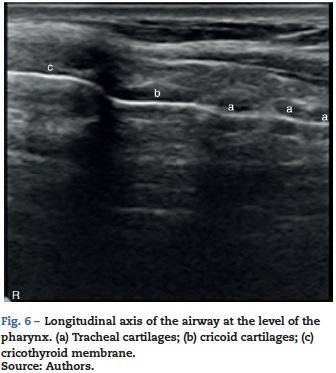

Cricothyroid membrane

A hypoechoic structure between the thyroid and the cricoid cartilages can be observed through a longitudinal section along the larynx (Fig. 6). Using color Doppler the blood vessels over the laryngeal and tracheal structures can be identified, to avoid the risk of puncturing the vessels when a trans laryngeal puncture is made.

Tracheal rings

Semicircular hypoechoic structures can be seen at the longitudinal axis (Fig. 6). The puncture sites are located between the tracheal spaces for percutaneous tracheostomy.